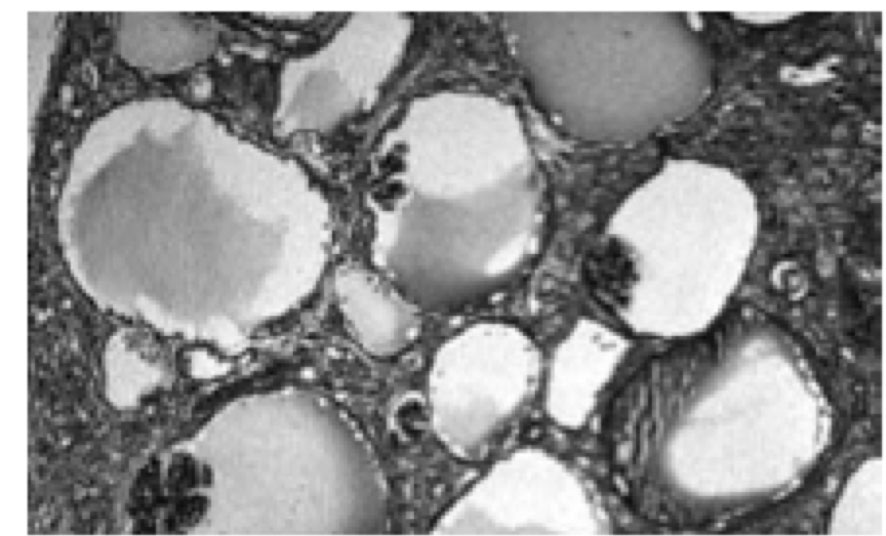

A 9-month-old girl, born to non-consanguineous parents, with normal antenatal ultrasound and no history of renal disease in the family was noticed to have occasional vomiting since birth. Gradually her vomiting increased associated with diarrhea at 4 months of life. On evaluation, she was found to have serum creatinine level of 3.3 mg/dL and potassium of 4.2 mEq/L. U/S showed left pelvic kidney and normally placed right kidney, which were of normal size with increased echogenecity and loss of corticomedullary differentiation. She was managed with IV fluids and peritoneal dialysis for 4 days at the local center. She improved symptomatically but had persistently elevated serum creatinine of 1.4-1.8 mg/dL.At 9 months, she weighed 5.25 kg, was anemic with no dysmorphic features. She was well hydrated but had acidotic breathing; blood pressure level was 80/60 mm Hg.Investigations showed serum creatinine of 2.0 mg/dL, sodium 143 mEq/L, potassium 4.6 mEq/L, chloride 115 mEq/L, bicarbonate11 mEq/L, total protein 7.9 g/dL, albumin 3.9 g/dL, cholesterol 334 mg/dL, calcium 9.0 mg/dL, phosphorus 2.7 mg/dL, alkaline phosphatase 1583 IU/L, uric acid 13 mg/dL, hemoglobin 6.1 g/dL and PCV 17%. Urinalysis showed specific gravity of 1.010, pH 5.0, albumin 3+ and occasional RBCs. The random urine protein was 397 mg/dL and creatinine 10 mg/dL; protein to creatinine ratio 39.7. U/S examination confirmed the previous findings. Micturating crystourethrogram showed no evidence of VUR.The patient was managed with oral sodium bicarbonate (5 mL three times a day) and oral allopurinol (25 mg twice a day). She received packed cell transfusion, followed by subcutaneous injections of erythropoietin (250 IU weekly), oral iron (5 mg/kg/day) and folic acid (2.5 mg/day). An ultrasound guided renal biopsy was done on the right kidney under general anesthesia. I/F examination showed insignificant deposits of IgM and C3c in the glomeruli.

Glomerulocystic kidney disease (GCKD) is a rare renal cystic disease characterized by glomerular cysts (limited to renal cortex and > 5% cystic glomeruli) and may be associated with renal dysplasia and renal failure in infancy.

In our case, the patient presented by renal insufficiency after an attack of gastro-enteritis. Loss of corticomedullary differentiation at the onset of the disease was not explained by gastro-enteritis. The patient developed, later on, proteinuria of glomerular origin in addition to other features of renal insufficiency. Biopsy was diagnostic.